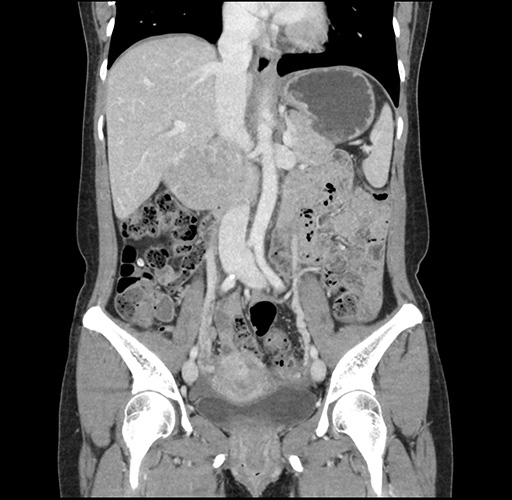

Imaging Analysis

Look through the patient's CT scan to identify any areas of concern for the necessary procedure.

Based on your CT findings, which issue(s) would give reason for "planned slowing down moment(s)" in this case?

Considering a standard left lateral sectionectomy procedure, what step(s) of the operation would you do differently in this case ?